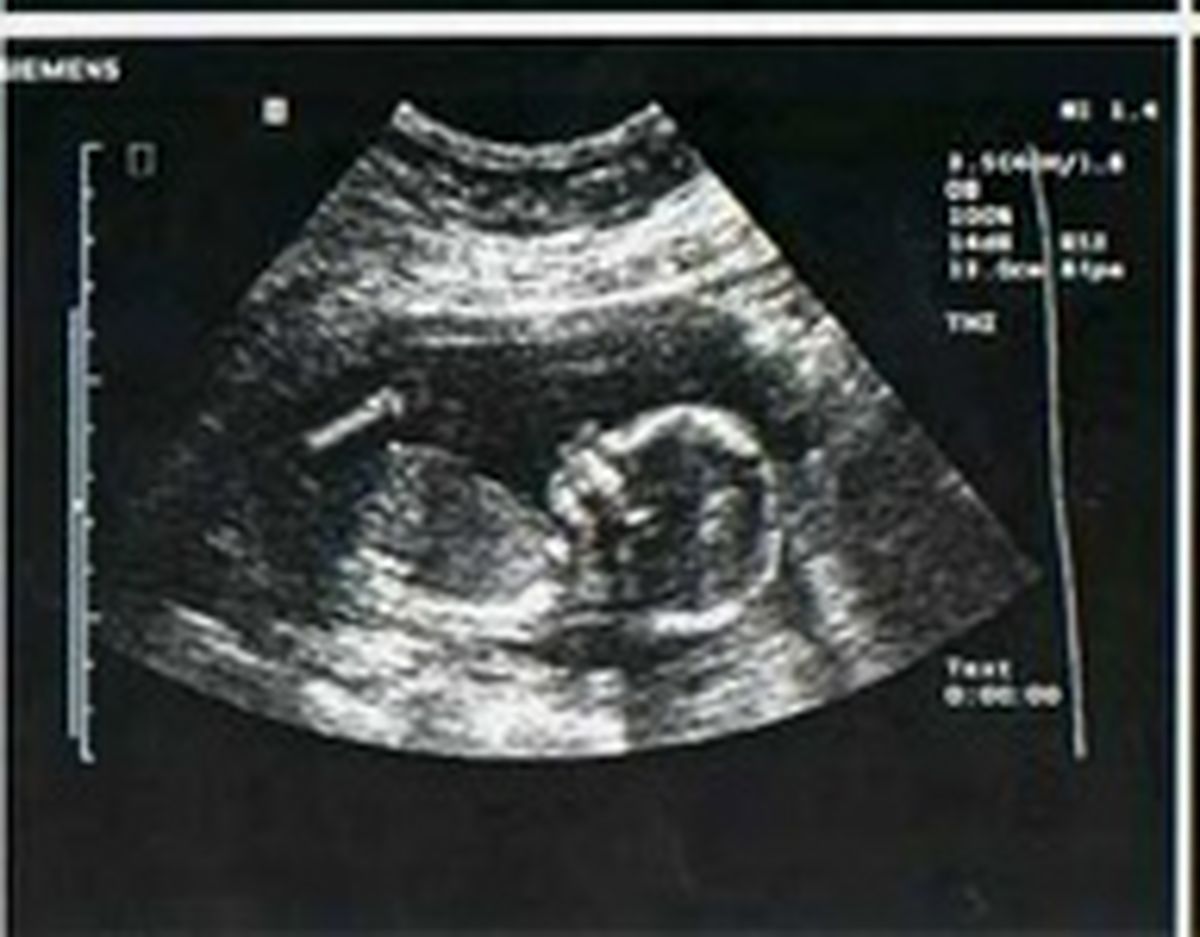

مدیرکل دفتر سلامت جمعیت، خانواده و مدارس وزارت بهداشت درباره نامه ای با عنوان "حذف غربالگری جنین از سامانه های الکترونیک"، توضیحاتی ارائه کرد.

دکتر سید حامد برکاتی اظهار داشت: این نامه به استناد تبصره ۳ ماده ۵۳ و ماده ۵۴ قانون حمایت خانواده و جوانی جمعیت تنظیم شده است. بر اساس این قانون، غربالگری و ثبت آن در سامانه های وزارت بهداشت نه تنها ممنوع نشده بلکه در ماده ۵۴ بر آن تاکید هم شده است.

وی افزود: در وزارت بهداشت، سامانه خاصی بر اساس ماده ۵۴ قانون حمایت خانواده و جوانی جمعیت در حال طراحی است و درخواست غربالگری، فرآیند انجام آن، نتیجه تصویربرداری(سونوگرافی) و آزمایشات مربوط به غربالگری در این سامانه باید ثبت شود.

برکاتی این را هم گفت که نامه نگاری مذکور برای سطح یک ارائه خدمات و سامانه های مربوط به آن بوده است. بر اساس قانون، درخواست غربالگری آنومالی های جنینی با عنایت به شرایط خاص آن در سطح یک ارائه خدمات بهداشتی قابل ارائه نیست و حتما درخواست غربالگری باید توسط متخصصین انجام شود و آیین نامه اجرایی نیز درهمین راستا تهیه شده است./اینا